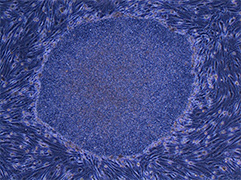

Professor Shinya Yamanaka’s group reported the establishment of mouse iPS cells by introducing 4 factors, Oct3/4, Sox2, Klf4 and c-Myc, into mouse skin cells in the journal “Cell.”

ⓒCenter for iPS Cell Research and Application,Kyoto University

2007 Human iPS cells announced

Professor Shinya Yamanaka’s group reported the establishment of human iPS cells by introducing 4 factors,Oct3/4, Sox2, Klf4 and c-Myc, into human skin cells in the journal “Cell.” Professor James Thomson’s group also reported human iPS cells established with a different method in another journal on the same day